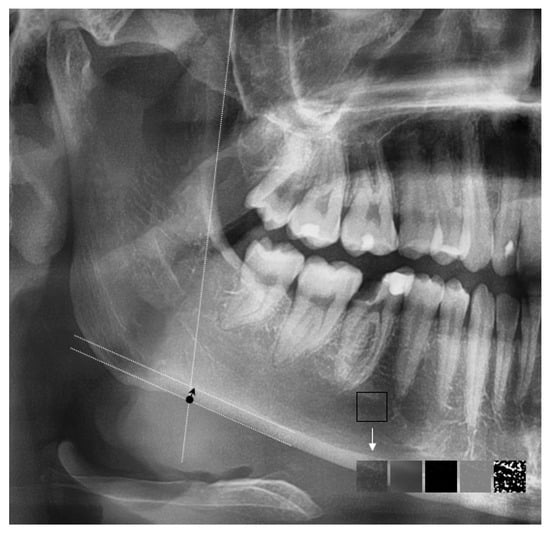

The antegonial index (AI) was determined and calculated employing the AudaxCeph program (Audax d.o.o., Ljubljana, Slovenia). This medical software for X-ray analysis allows the creation of customized two-dimensional measurements based on previously introduced anatomical landmarks. Within the AudaXCeph (Audax d.o.o., Ljubljana, Slovenia) software on panoramic X-ray, two lines were created for each image. The first line was parallel to the ascending ramus of the mandible (line of best fit), and the second line was parallel to the body of the mandible (Figure 1). At the intersection of the lines, the thickness of the compact plate of the lower edge of the mandible was measured.

Figure 1.

Panoramic cropped image with marked auxiliary lines to assess the thickness of the cortical plate of the lower edge of the mandible (Antagonial index—AI). Selected region of interest (ROI) enabling fractal analysis and the stages of image analysis. The black arrow—the compact bone; the white arrow—the process of transforming a region of interest into a binary version.

Fractal analysis (FCA) of the trabecular bone of selected regions of the mandible was performed using the ImageJ version 1.53k software (National Institutes of Health, Public Domain), employing the method described by White and Rudolph [17]. The selected regions of interest (ROI) of 60 × 60 pixels, located distally to the mental foramen, above the margin of the cortex and below the tips of the roots, were cropped from the X-ray image and stored for detailed further analysis (Figure 1). The above area was selected due to the lack of overlapping anatomical structures, such as the cervical spine, maxillary sinus or air between the hard palate and the base of the tongue. According to the authors, the selected anatomical location is the most reliable place for assessing cancellous bone. When selecting the ROI, locations that could represent a periapical lesion were avoided. To perform FCA, the given ROIs were converted into binary images in a series of modifications. At first, a Gaussian 5-pixel filter was applied to create a blurred version of the ROI’s image. Then, the blurred image was subtracted from the original image and normalized by setting the mean intensity at a value of 128. Finally, the normalized image was converted into a binary image. The fractal dimension of the binary image of the ROI was calculated by means of the FracLac plugin in the ImageJ software.